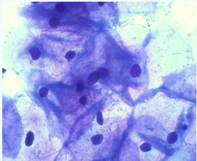

Микроскопия как метод исследования постоянно развивается в зависимости от технических достижений в области точной механики и оптики <#"588174.files/image001.jpg">